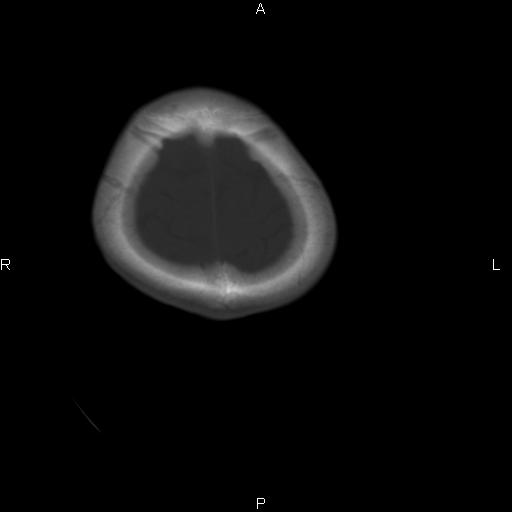

标题: CT27115:大家看一看,这孩子的颅骨表现? [打印本页]

标题: CT27115:大家看一看,这孩子的颅骨表现?

两名中学生打架,脑质内未见异常,未上传。

感觉第2个颅缝密度高,额顶部板障有点厚,正常变异?地中海贫血?